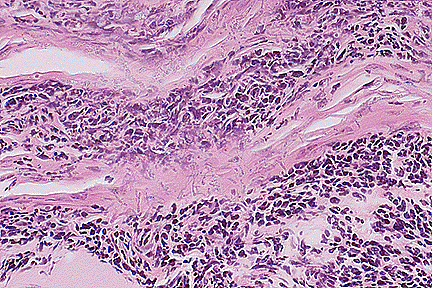

Bacterial embolus within glomerulus of a rhesus macaque. (40X, HE, 115K)

Sections of kidney reveal widely disseminated microabscesses which multifocally distort and replace normal architecture with 100-500 micron diameter foci composed of lytic cellular debris, degenerate neutrophils, histiocytes and lymphocytes. Abscesses are most often centered upon thrombosed vessels and often contain colonies of large cocci, accompanied by acute hemorrhage (serum, fibrin, and RBC's). Several infarcts extend from thrombosed vessels within the corticomedullary junction and radiate towards the capsular surface. Infarcts appear to be of mixed chronicity with varying degrees of coagulative necrosis, interstitial neutrophil and mononuclear cell infiltration, fibrosis, tubular epithelial regeneration, and parenchymal contracture. Tubules in severely affected areas are often dilated and contain neutrophils within a hyaline proteinaceous material. Glomerular changes include coagulative necrosis with capsular epithelial regeneration/hyperplasia, multifocal capillary thromboses with occasional bacterial colonization, multifocal mesangial cell proliferation, multifocal fibrinous synechiae, and rare glomerular sclerosis. Additional changes include perivascular nodular lymphocytic hyperplasia, mild inner medullary interstitial fibrosis, mild multifocal medullary interstitial mineral deposition, and mild nonsuppurative interstitial nephritis.

1. Kidney: Nephritis, suppurative, embolic, multifocal, moderate, with numerous gram positive cocci, bacterial emboli, and multiple infarcts, rhesus monkey (Macaca mulatta), primate.

2. Kidney: Glomerulonephritis, proliferative, diffuse, moderate.